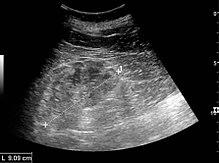

Renal ultrasonography of chronic renal disease caused by glomerulonephritis with increased echogenicity and reduced cortical thickness. Measurement of kidney length on the US image is illustrated by '+' and a dashed line.[9]

• Renal ultrasonography is useful for prognostic purposes in finding signs of chronic kidney disease, which however may be caused by many other diseases than glomerulonephritis.[9]